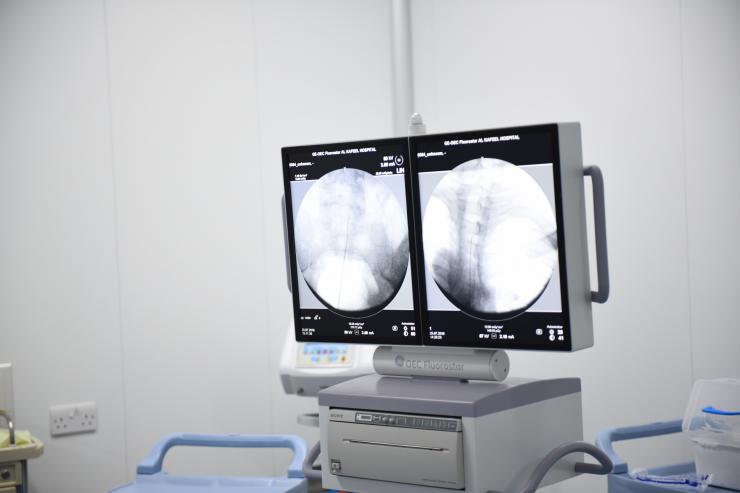

وقال مسؤول مركز علاج الالم والتخدير المناطقي الدكتور مرتضى جبارة أنه نجح بمساعدة فريقة الطبي من أعادة الأحساس والأتزان بالجلوس للمريضة بعد معاناة أستمرت اكثر من سنة، واوضح جباره قائلا: قمنا بعملية التحفيز الكهربائي الحركي الحسي مع النابض الحراري، وبدئنا من منطقة الضرر بالفقرة التاسعه والعاشرة من المنطقة الصدرية وصولاً الى المنطقة العجزية.